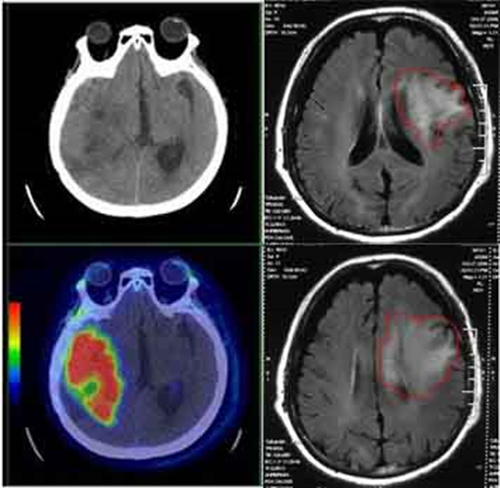

CT虽然有些辐射,但是现在头痛难忍的情况更加紧急!最终头颅CT揭示了答案:脑部胶质瘤!

在患者的大脑里不仅存在着一个可能是胶质瘤的东西,而且已经出现了脑水肿,所以患者才会突然出现头痛呕吐!

最后这位脑胶质瘤患者住进了脑外科病房,在经历过一系列手术等治疗后同样康复出院!